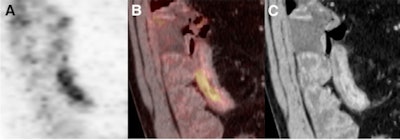

| The images depict intramural water attenuation on PET/CT enterography. Coronal PET image (A) shows increased uptake of FDG in distal ileum (SUVmax = 7). A fused PET/CT enterogram (B) shows FDG uptake in bowel wall. Coronal reformatted CT enterogram (C) shows abnormal segments with water attenuation by visual assessment in distal ileum (mural enhancement, 135 HU; wall thickness, 11 mm). Images courtesy of the Journal of Nuclear Medicine. |

Mean mural enhancement also was significantly higher in abnormal segments than in normal segments (113.4 ± 23.7 HU), with abnormal mural enhancement significantly higher in the ileum than in the colon (117.9 ± 21.7 HU and 104.2 ± 25.3 HU, respectively).

In addition, SUVmax was significantly higher in abnormal segments than in normal segments (5.0 ± 2.5), with no significant difference in SUVmax between segments of ileum and segments of colon.